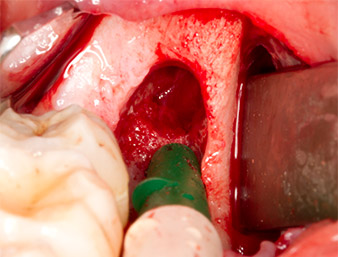

Nach Leitungs- und Lokalanästhesie wurde das Operationsfeld für einen bukkal-retromolaren Zugang weichgewebig eröffnet und dargestellt (Abb. 3).

Das Gewebe über dem Wurzelrest war nicht vollständig verknöchert und bestand zu einem großen Teil aus entzündlich verändertem Granulationsgewebe (Abb. 4).